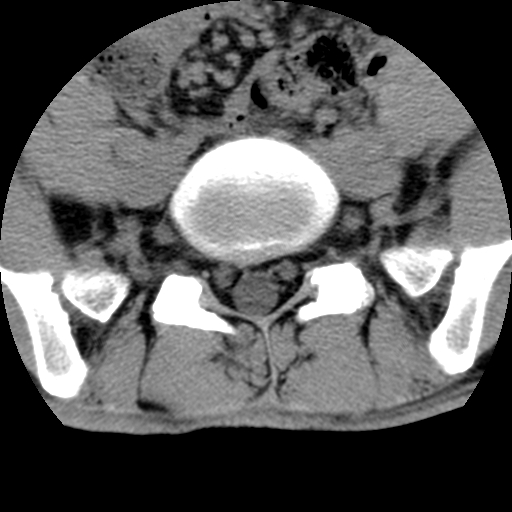

男,腰背痛

本人诊断1tb2包虫,请会诊

1)右侧竖脊肌稍低密度肿块伴钙化(性质待定),不排除肿瘤可能;建议行进一步检查。2)腰椎间盘突出。

1.右侧竖脊肌软组织肿块伴团块状钙化,首先考虑血管瘤可能性大;建议行进一步检查;2。腰椎间盘突出。